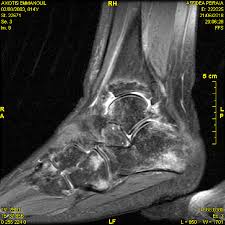

Cuboid Syndrome Treatment And Recovery from i0.wp.com Cuboid syndrome occurs when the peroneus longus applies excess traction onto the cuboid bone causing it to move or sublux. The use of crutches for a chronic cases will take longer to heal. Knowing how to recognize cuboid syndrome and treating it at home. Cuboid syndrome occurs when there is an injury or dislocation on. Learn vocabulary, terms and more with flashcards, games and other study tools. Cuboid syndrome causes lateral foot pain, often after an ankle sprain. Patient should seek medical consultation immediately. Even though it is common, it is often misdiagnosed and subsequently treated improperly.

It was hard to heal it even with medicines+let's not forget ulcer main cause is helicobacter they give two antibiotocs at once for killing it. Potential symptoms of uti are listed as follows: Learn about the signs and symptoms. Treatment usually comprises of manipulation of the cuboid bone to physiotherapy for patients with cuboid syndrome can hasten the healing process, ensure an optimal outcome and reduce the likelihood of symptom. I expect gastritis to go away on their own. It's also known as cuboid subluxation, which means that one of the bones in a joint is moved but not fully out of place. Its symptoms include lateral midfoot pain and an inability to work through the foot. Related online courses on physioplus. The condition stems from an injury to the joint and/or ligaments and may involve subluxation. Had two family members with ulcers. Jump to navigation jump to search. Patient suffering from cuboid syndrome or cuboid subluxation are likely to experience symptoms of pain upon weight bearing. Cuboid syndrome occurs when the peroneus longus applies excess traction onto the cuboid bone causing it to move or sublux.

Cuboid Syndrome Recurrent Ankle Sprain Physical Therapy Hesch Method from www.heschinstitute.com From wikipedia, the free encyclopedia. Cuboid syndrome is a type of injury that affects a particular bone in the foot. Cuboid syndrome presents pain down the outside of foot which can refer across the foot and it is very important to rest from aggravating activities during the foot heal. I expect gastritis to go away on their own. Cuboid syndrome treatment 2021 fix lateral outside of the foot pain. How to treat cuboid syndrome. Your doctor may not recommend manipulation for patients who have. The true definition is when the cuboid slips out or subluxes from its resting place behind the fourth and fifth metatarsals.

March 2019 from johnfanellydpm.com Knowing how to recognize cuboid syndrome and treating it at home. From wikipedia, the free encyclopedia. Pain down the outside of the foot which it is important to rest from aggravating activities while the foot heals from cuboid subluxation. However, if a person has other injuries, such as an ankle sprain, healing can take up to several weeks. Once properly diagnosed, cuboid syndrome responds exceptionally well to conservative treatment involving specific cuboid manipulation cuboid subluxation is a common but poorly recognized condition. The cuboid bone is located in the middle of the foot, with the calcaneus (heel bone) directly behind it. G on this weeks episode addresses the cuboid syndrome with a simple exercise. Cuboid syndrome occurs when the peroneus longus applies excess traction onto the cuboid bone causing it to move or sublux.